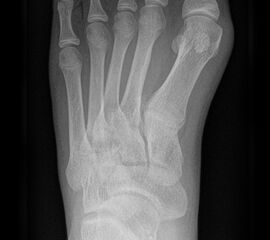

Die folgenden Bilder zeigen die belastete Röntgenaufnahmen des linken Fußes einer jungen Patientin zu Beginn der Therapie und nach 6 Monaten Training. Erkennbar ist die höhere muskuläre Verspannung des Fußes mit verbesserter Stellung der milden Hallux valgus Deformität.